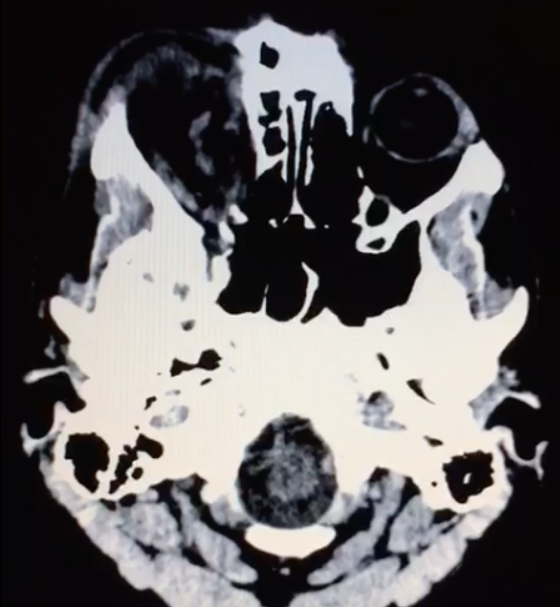

- Tomografia de crânio estrutura captante com a invasão de contraste. Ausência de coleção purulenta e presença de lesão em topografia de seio cavernoso e evidência da veia oftálmica superior. Além disso, a TC mostra sinais de traumatismo prévio (fratura frontal).

As fístulas arteriovenosas (FAVs) da região do seio cavernoso (SC) são lesões raras e difíceis de diagnosticar. Os principais sinais e sintomas são proptose, hiperemia conjuntival, quemose, paralisia dos III, IV, V e VI nervos cranianos, ptose palpebral, glaucoma, redução da acuidade visual e cefaleia. Nas fístulas carótido-cavernosa existe um defeito na parede da artéria carótida interna (ACI) que a comunica diretamente com o SC e, em consequência, um shunt arteriovenoso de grande volume. Na TC podemos identificar dilatação ou trombose da veia oftálmica superior (VOS), proptose, contrastação precoce do SC, espessamento da musculatura extraocular e edema da gordura periorbitária3.

As FCC diretas apresentam na maioria dos casos um alto débito ao contrário das FCC indiretas que em termos hemodinâmicos são de baixo débito. Etiologicamente as primeiras são traumáticas em cerca de 75% dos casos podendo, no entanto, ocorrer espontaneamente. As FCC indiretas são geralmente espontâneas, ocorrendo classicamente em mulheres pós-menopáusicas ou em grávidas. O diagnóstico é efetuado pela clínica e por Tomografia Computadorizada de crânio e/ou Ressonância Magnética Nuclear das Órbitas, onde o sinal mais específico é a dilatação da veia oftálmica superior. No entanto, o diagnóstico definitivo, a caracterização da fístula e o planejamento do tratamento endovascular só são possíveis com a angiografia cerebral6.